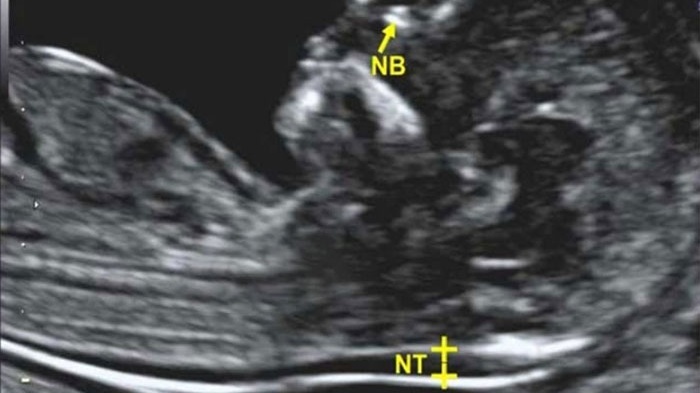

Siêu âm đo độ mờ da gáy là phương pháp kiểm tra vùng da gáy của thai nhi nhằm xác định trẻ có nguy cơ mắc các dị tật hoặc hội chứng Down hay không.

Phần lớn siêu âm được sử dụng để đo độ mờ da gáy cho thai nhi thường là siêu âm 2D. Thông thường siêu âm 2D chỉ cho các hình ảnh lát cắt mỏng và hình ảnh thu theo 2 chiều nhưng cũng đủ để cung cấp các thông tin có liên quan về mặt lâm sàng cho các bác sĩ.

Để đo độ mờ da gáy, bác sĩ sẽ tiến hành đo theo chiều từ đỉnh đầu đến cuối xương sống của thai nhi rồi tiến đến sau gáy. Lúc này, các mẹ sẽ thấy có khoảng mờ sau gáy là một đường màu trắng xuất hiện khu vực xung quanh có màu tối hơn. Qua phần màu trắng đó bác sĩ xác định được nguy cơ mắc bệnh dị tật ở thai nhi. Ngoài ra, trên màn hình bạn còn có thể thấy các bộ phận khác như tay, chân, đầu,… của bé và cũng thấy được các điểm bất thường ở bụng hay hộp sọ của thai nhi.